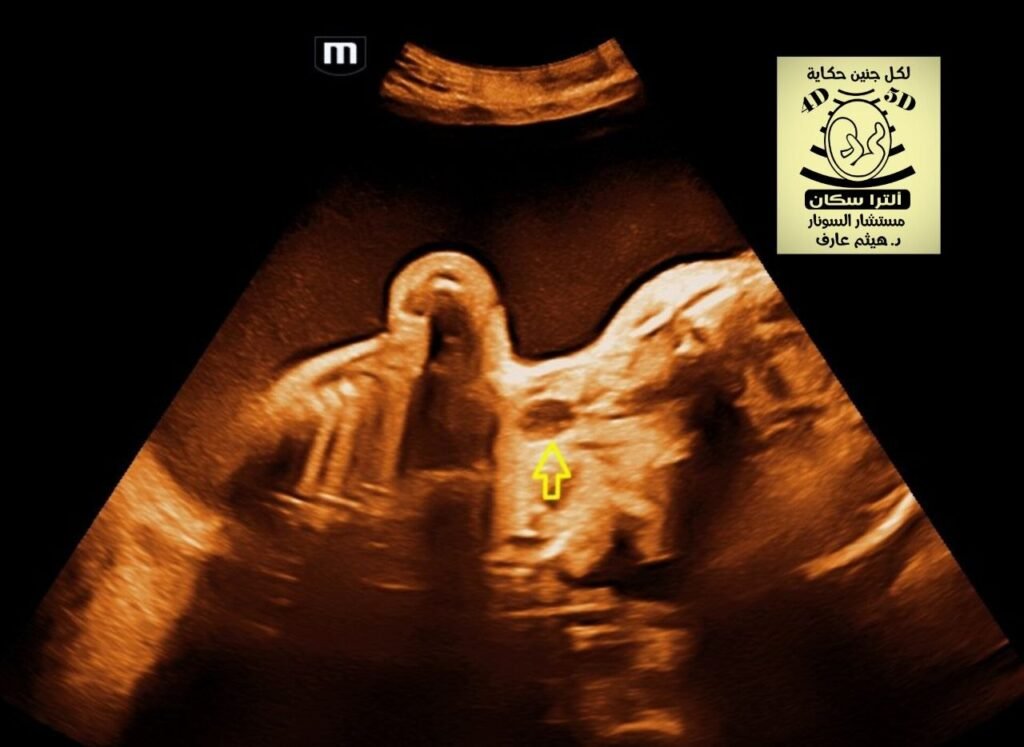

esophageal pouch sign fetal ultrasound

In fetal ultrasound, the

oesophageal pouch sign (or “upper neck pouch sign”) is a direct sonographic marker for esophageal atresia (EA). It is characterized by the visualization of a fluid-filled, blind-ending proximal esophagus that distends during fetal swallowing.

• Appearance: A transient, anechoic (fluid-filled) cystic structure in the fetal neck or upper mediastinum.

• Dynamic Nature: The pouch typically enlarges as the fetus swallows amniotic fluid and then empties or disappears as the fluid is regurgitated.